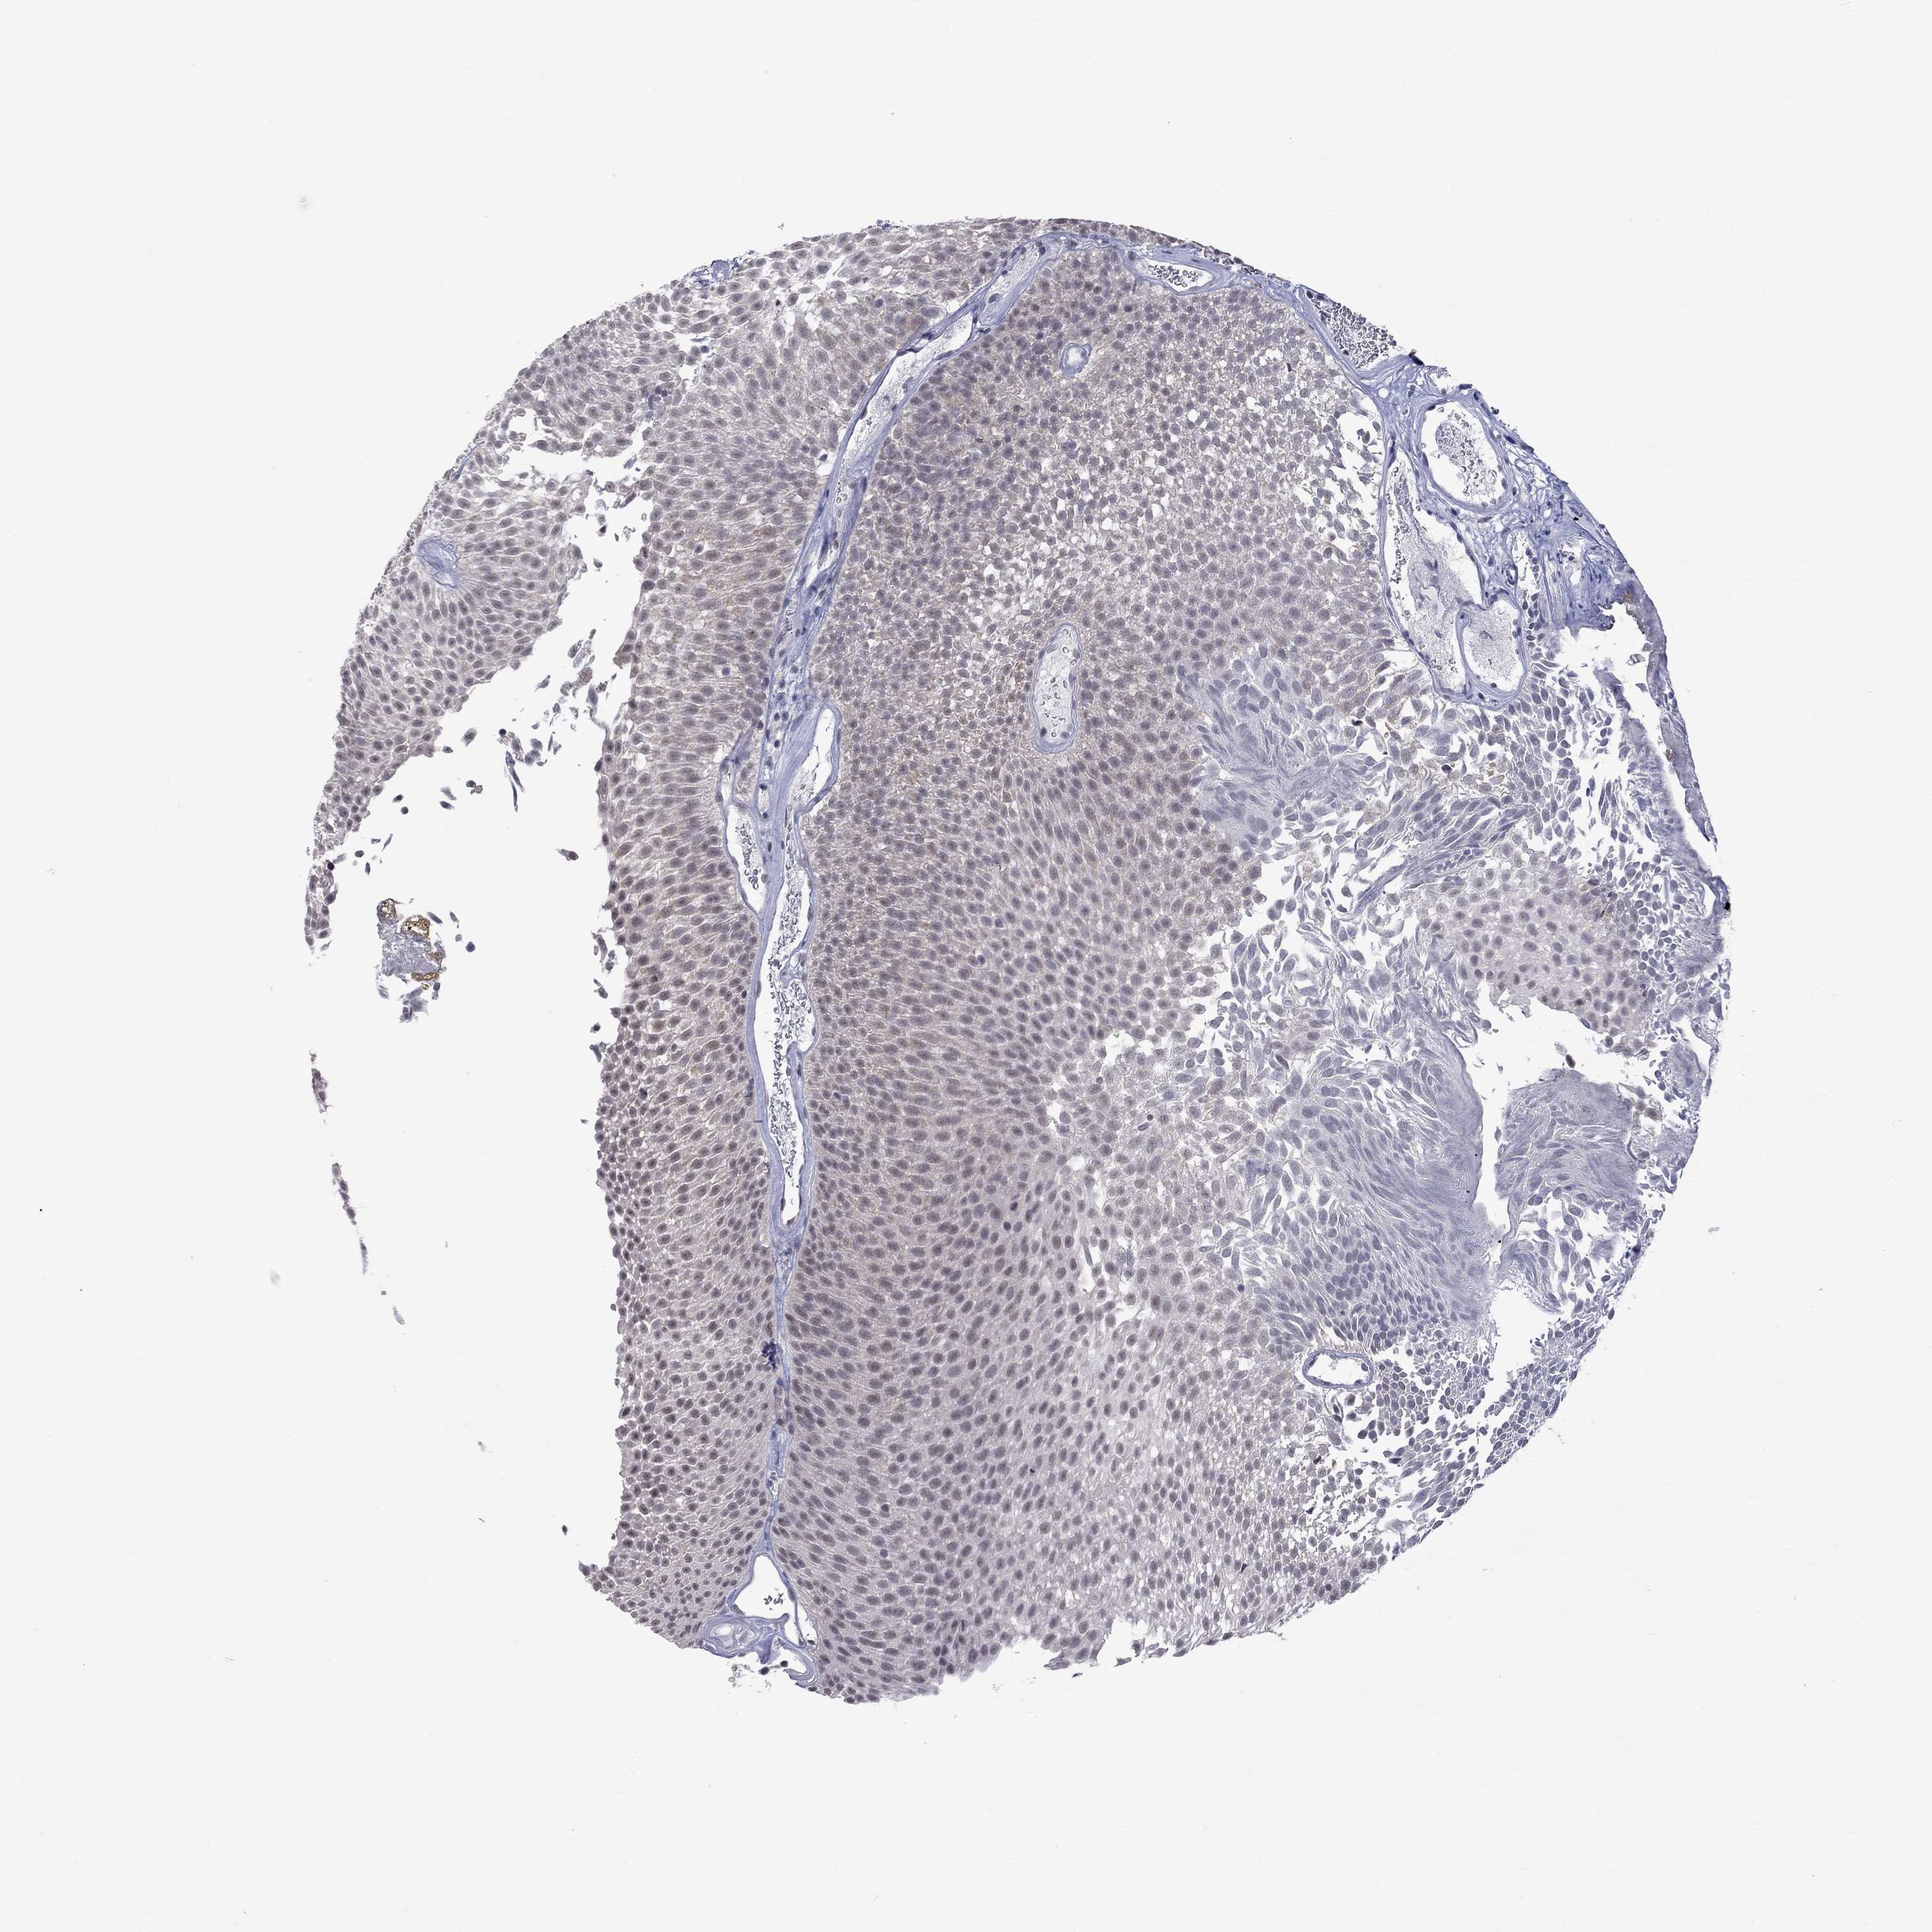

UROTHELIAL CANCER - Protein expressioni

A mouse-over function shows sample information and annotation data. Click on an image to view it in a full screen mode. Samples can be filtered based on level of antibody staining by selecting one or several of the following categories: high, medium, low and not detected. The assay and annotation is described here.

Note that samples used for immunohistochemistry by the Human Protein Atlas do not correspond to samples in the TCGA dataset.

Antibody stainingi

Antibody staining in the annotated cell types in the current human tissue is reported as not detected, low, medium, or high, based on conventional immunohistochemistry profiling in selected tissues. This score is based on the combination of the staining intensity and fraction of stained cells.

Each image is clickable and will lead to virtual microscopy that enables deeper exploration of all samples and also displays staining intensity scores, fraction scores and subcellular localization as well as patient and tissue information for each sample.

Antibody HPA014476

Antibody HPA058645

Staining

High

Medium

Low

Not detected

Intensity

Strong

Moderate

Weak

Negative

Quantity

>75%

75%-25%

<25%

None

Location

Nuclear

Cytoplasmic/membranous

Cytoplasmic/membranous,nuclear

Urothelial carcinoma, High grade

Urothelial carcinoma, Low grade